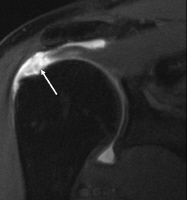

When one or more of the rotator cuff tendons is torn, the tendon no longer fully attaches to the head of the humerus. Most tears occur in the supraspinatus muscle and tendon, but other parts of the rotator cuff may also be involved.

To diagnose a rotator cuff tear, your doctor will give you a thorough physical exam. He or she will want you to move your arm in different directions to see what causes pain. In addition, your doctor might want to order the following tests:

- MRI (Magnetic Resonance Imaging)